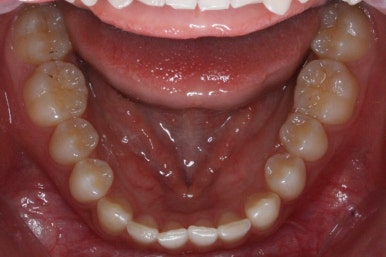

마무리 때의 사진입니다.

윗니만 부분교정하였지만 교합에도 이상 없이 매복되었던 송곳니는 매우 잘 위치를 잡았습니다.

송곳니 부위는 다시 틀어지지 않게 하기 위해 유지철사를 붙여주었습니다.

총 치료기간은 20개월 소요 되었습니다.

부산매복치아교정 상악 부분교정을 통해 매복치를 교정해준 이번 치료의 전후사진 비교입니다.

썩은 유치 대신 영구치 송곳니는 매우 자연스럽게 위치되었습니다. 아랫니는 교정하지 않았기 때문에 약간 삐뚠 느낌은 남아있지만 맞물림은 크게 문제가 없게 마무리 되었습니다.